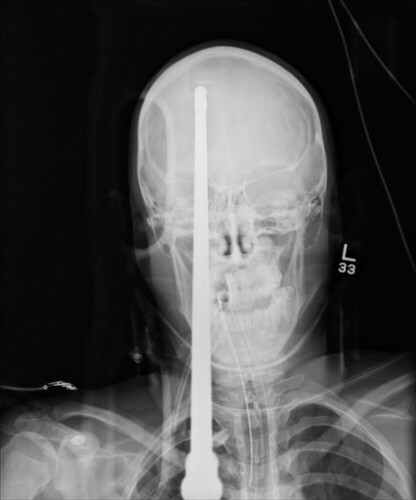

Florida teen recovering after being shot through head with spear

A FLORIDA TEENAGER is recovering in hospital after he was accidentally shot through the head with a spear by his friend during a fishing trip.

Doctors at the Jackson Memorial Hospital’s Ryder Trauma Center said yesterday that it took three hours to remove the spear from the 16-year-old’s brain.was rushed to hospital earlier this month with about 36 inches (3 feet) of spear protruding from his head. The projectile was accidentally fired by his friend as he was loading a spear gun.

The spear entered his forehead about two inches above his right eye and went through the back of his skull. Part of the visible section of spear was cut off to allow the teen to undergo cranial scans.

Doctors at the Jackson Memorial Hospital’s Ryder Trauma Center said yesterday that it took three hours to remove the spear from the 16-year-old’s brain.

The spear passed through the right hemisphere of his brain, missing major blood vessels, and doctors believe he could make a close to full recovery, ABC News reports. Although he does not remember the incident, the teenager has woken from his surgery and has spoken a few words.